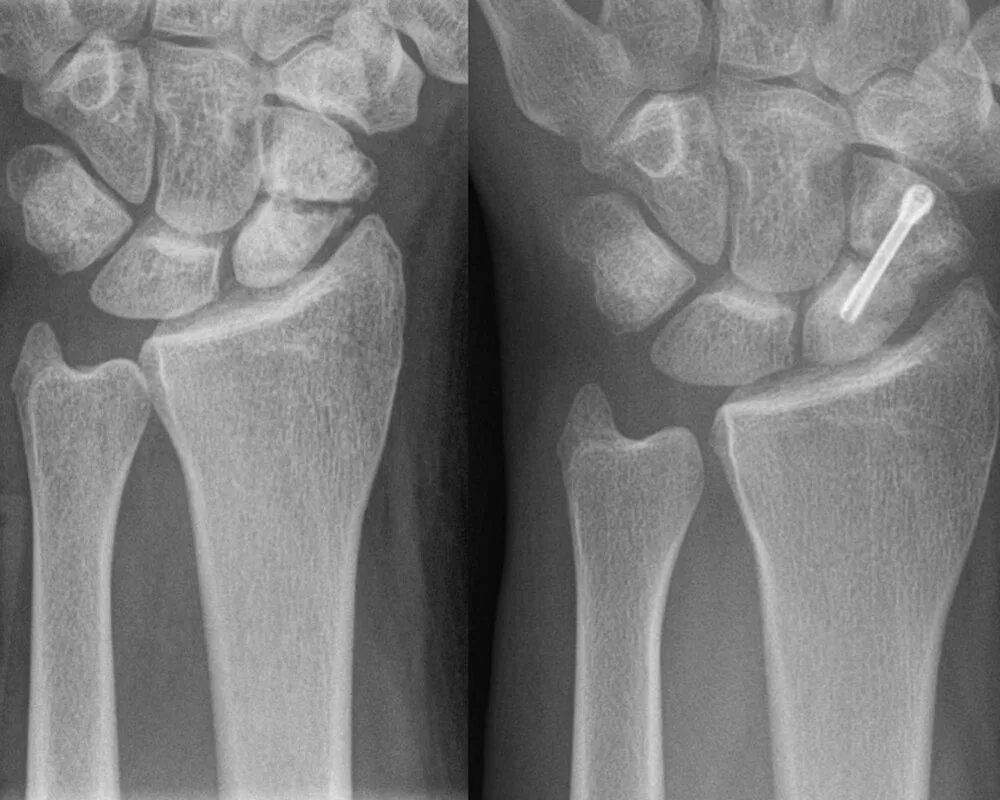

Срослась п и ж